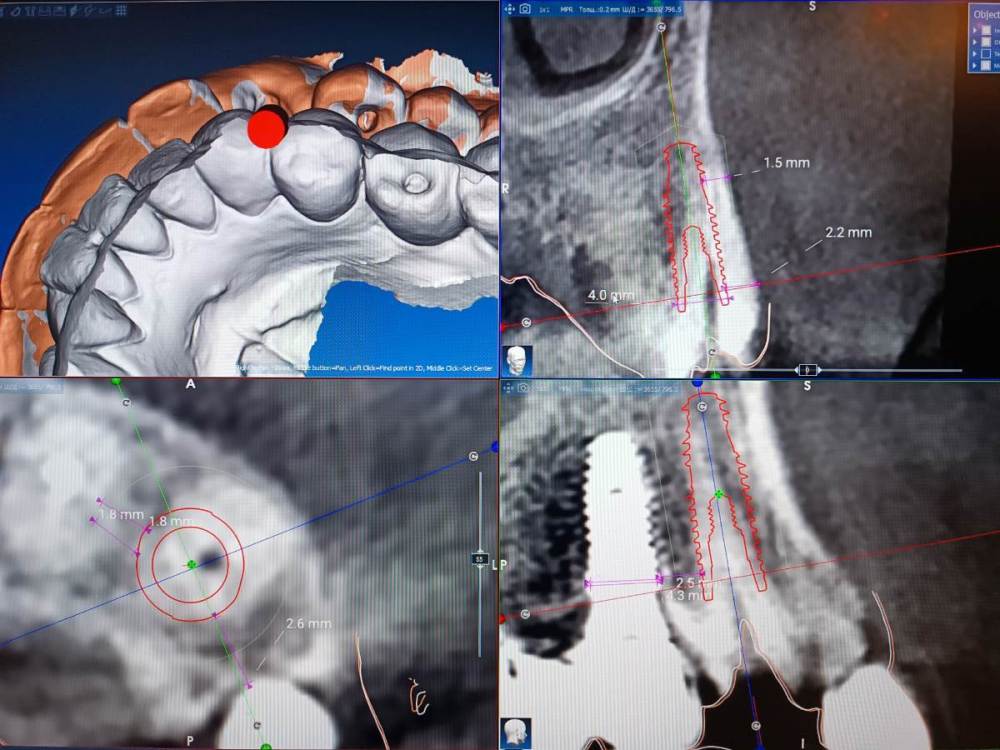

Fin Опубликовано 2 января, 2024 Поделиться Опубликовано 2 января, 2024 Коллеги всех с новым годом ?. Как считаете какое расстояние сейчас актуально между двумя имплантами?На данный момент есть установленная 4 ка но пациенту планируется одномоментная имплантация клыка.Сейчас по примерке расстояние получается 2 мм. Как бы Вы поступили в данном случае? Ссылка на комментарий

АнтонТЛТ Опубликовано 2 января, 2024 Поделиться Опубликовано 2 января, 2024 А если в лунку сместить? Ссылка на комментарий

Fin Опубликовано 2 января, 2024 Поделиться Опубликовано 2 января, 2024 2 часа назад, АнтонТЛТ сказал: А если в лунку сместить? Имеете ввиду вестибулярно? Ссылка на комментарий

АнтонТЛТ Опубликовано 2 января, 2024 Поделиться Опубликовано 2 января, 2024 Да, расстояние может получше будет? Ссылка на комментарий

Fin Опубликовано 3 января, 2024 Поделиться Опубликовано 3 января, 2024 18 часов назад, АнтонТЛТ сказал: Да, расстояние может получше будет? Да становится немного лучше но создает новую проблему одномоментной имплантации.Как вариант взять неодент 3.75, но не знаю выдержит ли. Ссылка на комментарий